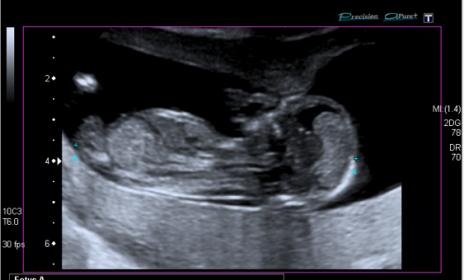

Boy lean from first pic. Not sure though. Any more pics?

I am torn 50/50 for me....maybe a slight slight lean girl.